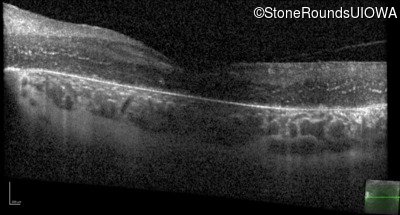

Optical Coherence Tomography - Left - 20/100 -2

Exemplar / OCT Stack

OCT Stack